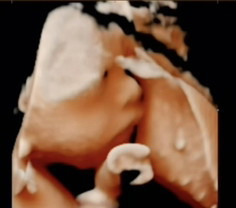

หนุ่มน้อนในวัย 30วีค ยิ้มกรุ้มกริ่มในท้องแม่ ❤️🫶🧸